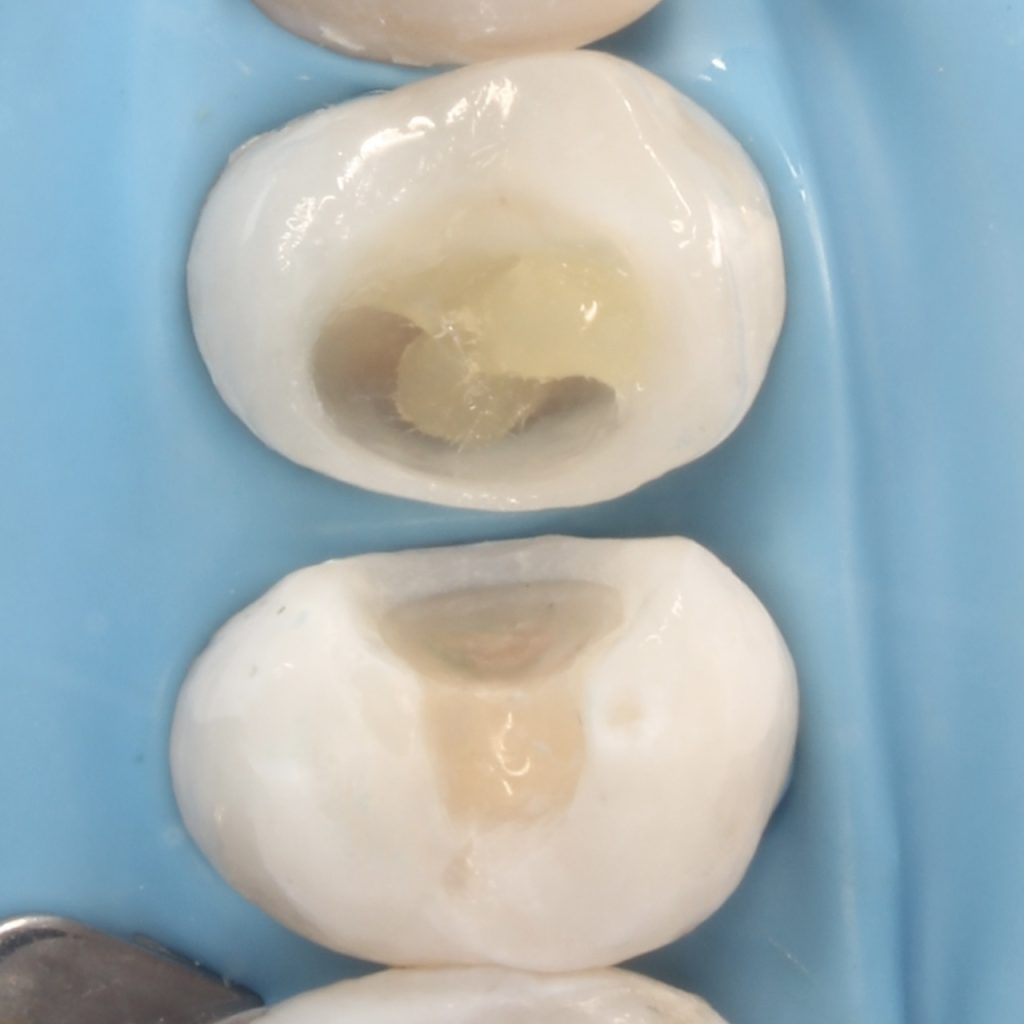

A 22 years old patient came to the clinic suffering from severe spontaneous pain. The diagnosis was acute irreversible pulpitis. The use of CDD is crucial here to ensure the CRE. After finishing endodontic treatment we used polyethylene fibers to enhance the bond strength and the strength of the tooth. Then the use of glass fibers (ever X composite) as a dentin replacement material before the final layer. After finishing. Polishing protocol with eve twist was done to gain the final polish